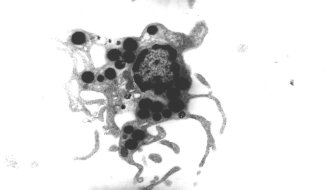

Effect of obesity and uptake of fat into dendritic cells

Some differences in DC properties and functions are related to obesity and to the distribution of fat. Increased scavenger receptor expression and fat-storage in DC have been found particularly in cancer and contribute to loss of DC stimulatory function and suppression of immune activity by DC4,5. Systemic differences in fat and fat metabolism in DC themselves in gut inflammation6 and in colorectal cancer which affect their immune functions are being identified4.